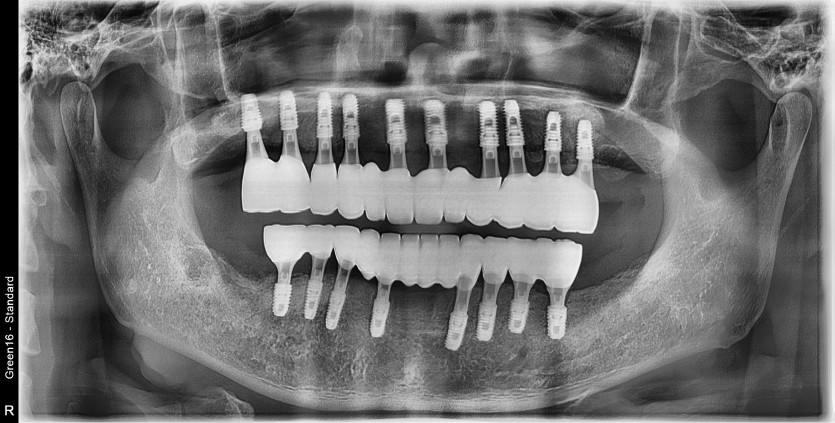

만 49세 전체 임플란트 증례

전체 임플란트 증례입니다.

18개의 임플란트로 완성하였습니다.